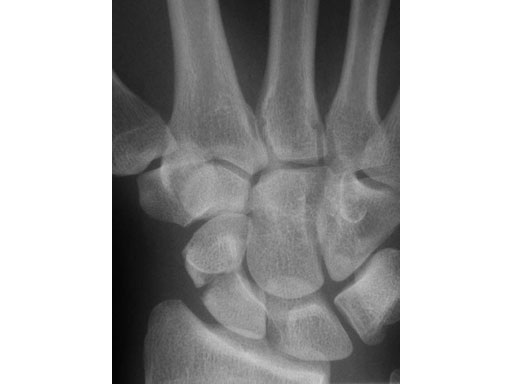

24-year-old male with an acute scaphoid wrist fracture treated by percutaneous fixation with a 3.0 mm headless compression screw under regional anesthesia.

Fig 1 Preoperative x-ray.